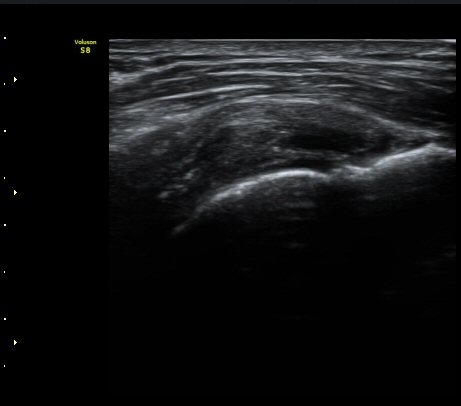

¿À±¸µ¹±â Ⱦ´Ü¸é°Ë»ç»ó ¿Áµ¹±â ¾Æ·¡, ³»Ãø, °ß°©ÇÏ±Ù°Ç Ç¥Ãþ¿¡¼­ ¼ö¾×Àú·ù°¡ °üÂûµÈ´Ù

(±×¸² 3, 4).